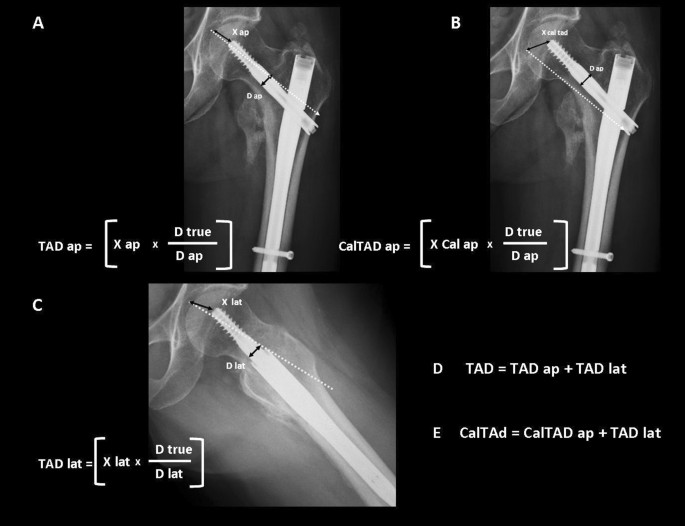

TAD and CalTAD measurements were performed with the aid of Carestream Vue Picture Archiving and Communication system (PACs, version 12.2.5.00397) software. TAD and CalTAD were calculated on postoperative x-rays in two projections, namely a standard anteroposterior projection of the lower limbs rotated internally by 15°, and cross-table lateral projections with the contralateral limb flexed and abducted. A single observer (a consultant trauma surgeon) measured the TAD and the CalTAD, the screw position according to Cleveland method, and the fracture reduction, in order to eliminate inter-observer variability. Tad and CalTAD have been calculated with the formula shown in Fig. 1.

(A) Tip-apex distance calculated on anteroposterior radiograph (TAD ap); (B) Tip-apex distance as referenced to the calcar calculated on the anteroposterior radiograph (CalTAD ap); (C) Tip-apex distance calculated on the lateral radiograph (TAD lat); (D) Tip-apex distance (TAD); (E) Calcar-referenced tipapex distance (CalTAD). D true is the known diameter of the lag-screw (10.5 mm for Gamma3 nail, 15.5 mm for Trigen Intertan nail). D ap is the calculated diameter of the lag-screw on the anteroposterior radiograph. D lat is the calculated diameter of the lag-screw on the lateral radiograph.